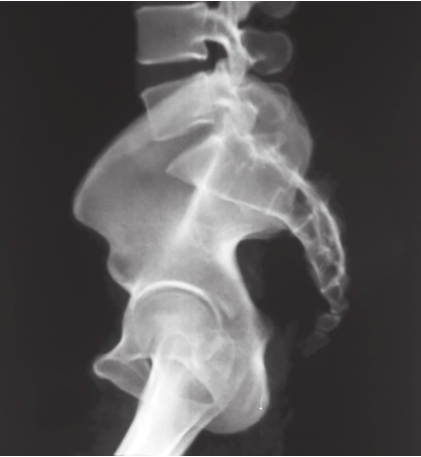

在压缩型损伤中,骨盆后环损伤侧的髂骨翼向内旋,在X线正位片中,其髂骨翼宽度(测量髋臼上方髋骨或骶髂关节至髂前上棘之间距离)比对侧窄。由于髂骨扭转,其闭孔由斜变正,显得大于对侧,耻骨联合被挤离中线,向对侧移位。伤侧髂骨向上脱位或移位多者可造成耻骨联合上下分离。在分离型损伤中,后环伤侧髂骨翼向外旋,由斜变平,显像宽于对侧,耻骨联合被牵拉离开中线向伤侧移位,或出现耻骨联合分离,外旋髂骨的闭孔更斜,故显像比对侧小。此类骨折损伤严重,常合并休克,手术时需要前后联合入路(图2-10)。

图2-10 骨盆扭转变形X线片

可见右侧耻骨上、下支骨折,耻骨联合分离,右侧骨盆向上移位,提示右侧骨盆后环损伤,向外旋转变形。